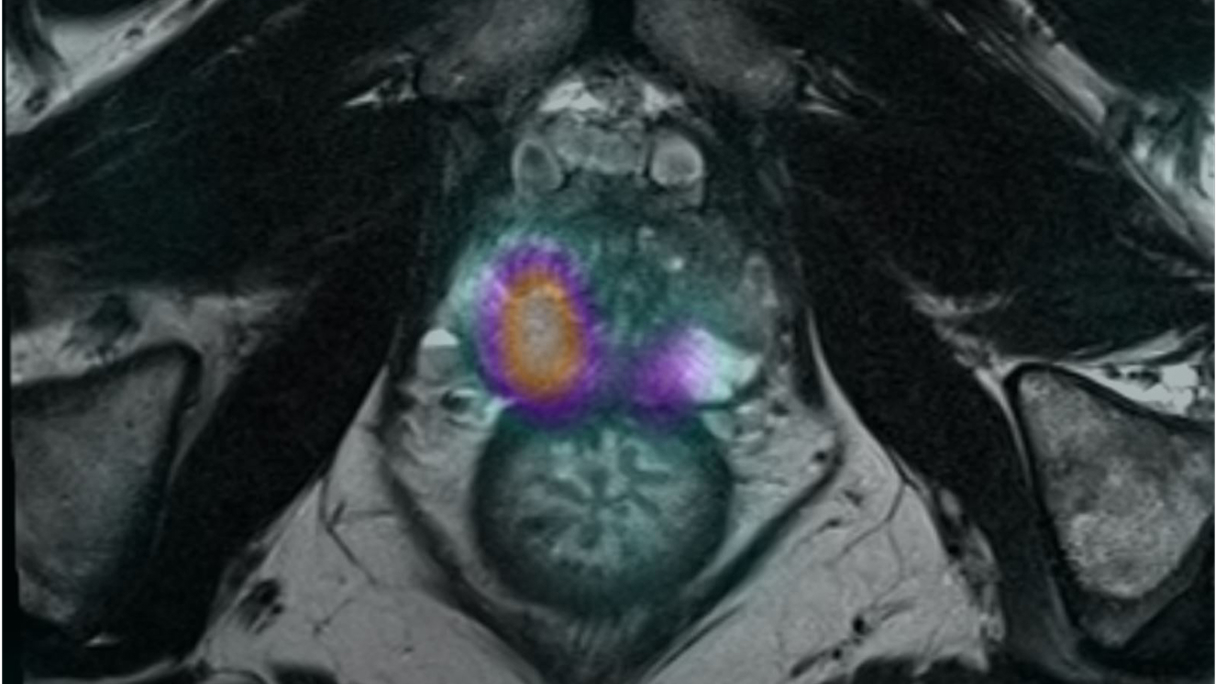

La velocità di progressione della fibrosi cardiaca: un nuovo orizzonte

La velocità di progressione della fibrosi cardiaca emerge come un nuovo e cruciale indicatore prognostico nella cardiomiopatia ipertrofica. Un recente studio evidenzia come l’LGE rate sia più predittivo degli eventi avversi rispetto alla semplice estensione della fibrosi, aprendo nuove prospettive per il monitoraggio e la gestione terapeutica dei pazienti.